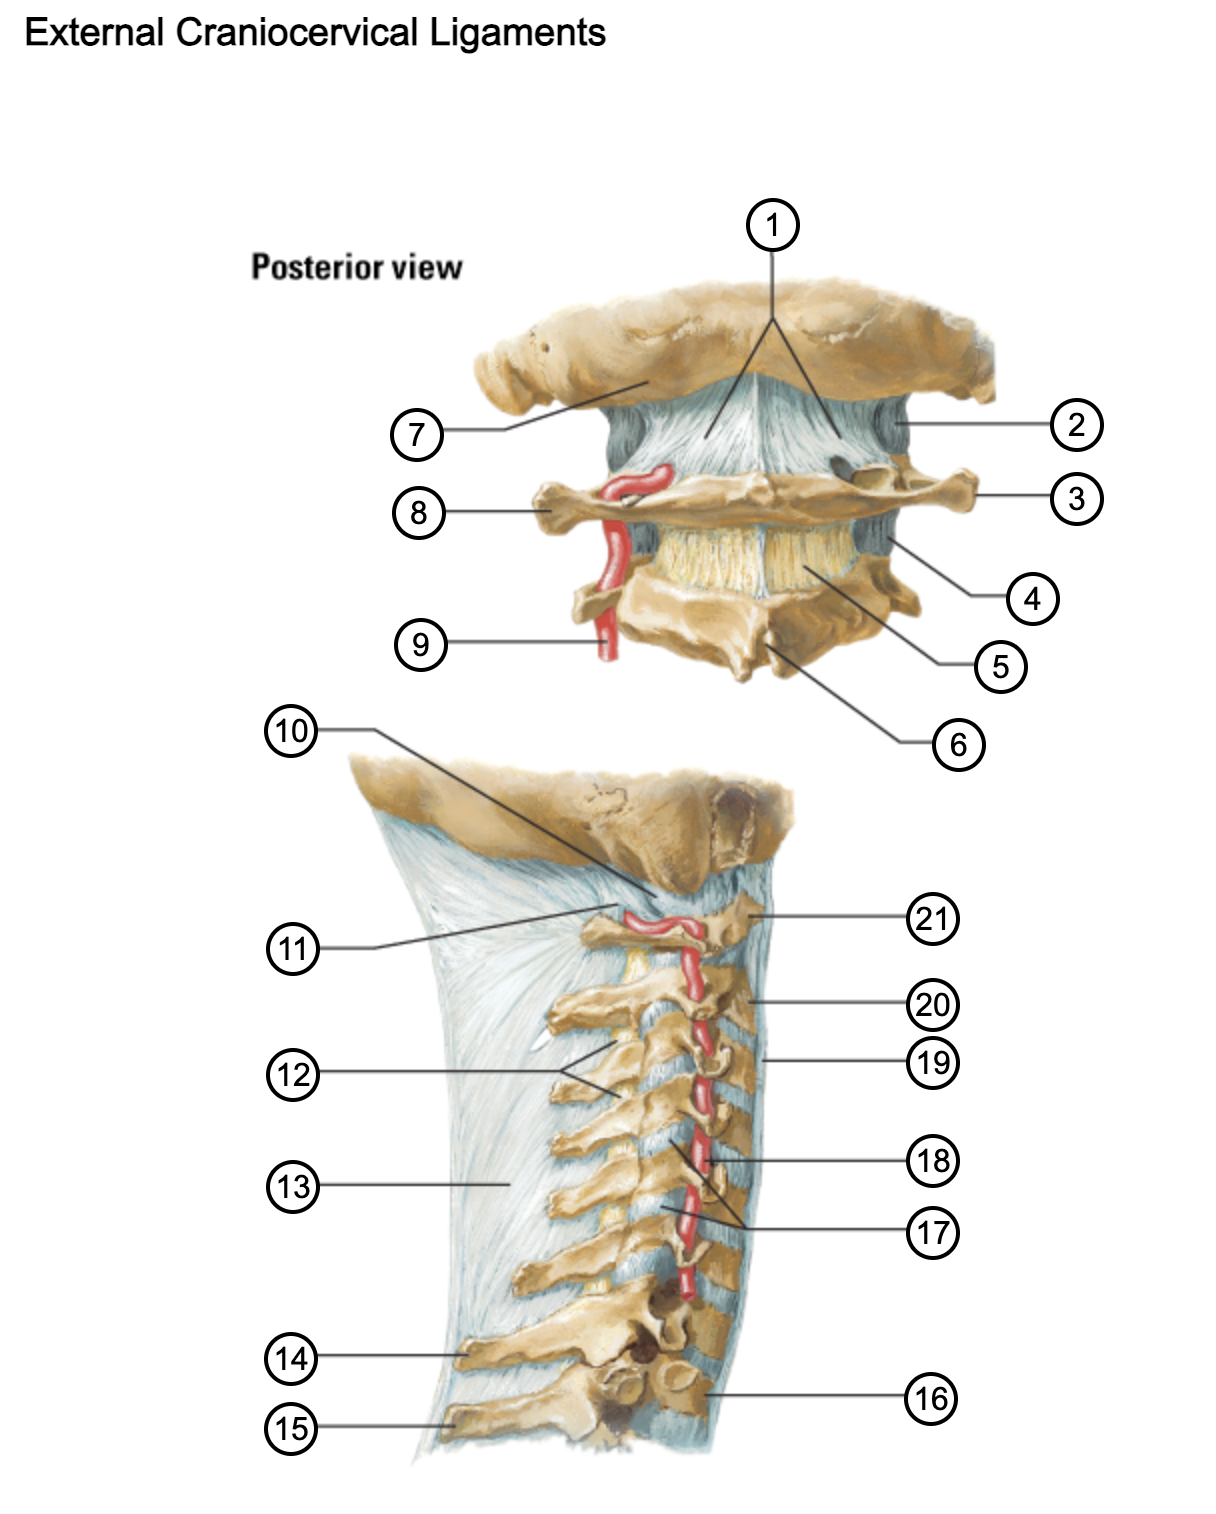

1

posterior antlantooccipital membrane

2

capsule of atlantooccipital joint

3

transverse process of atlas (C1)

4

capsule of lateral atlantoaxial joint

5

ligamenta flava

6

spinous process

7

occipital bone

8

transverse process of atlas (C1)

9

vertebral artery

10

capsule of atlantooccipital membrane

11

posterior atlantooccipital membrane

12

ligamenta flava

13

nuchal ligament

14

spinous process of C7 vertebra

15

spinous process of T1 vertebra

16

T1 vertebra

17

zygapophysical joints (C4-5 and C5-6)

18

vertebral artery

19

anterior longitudinal ligament

20

body of axis

21

Atlas (C1)